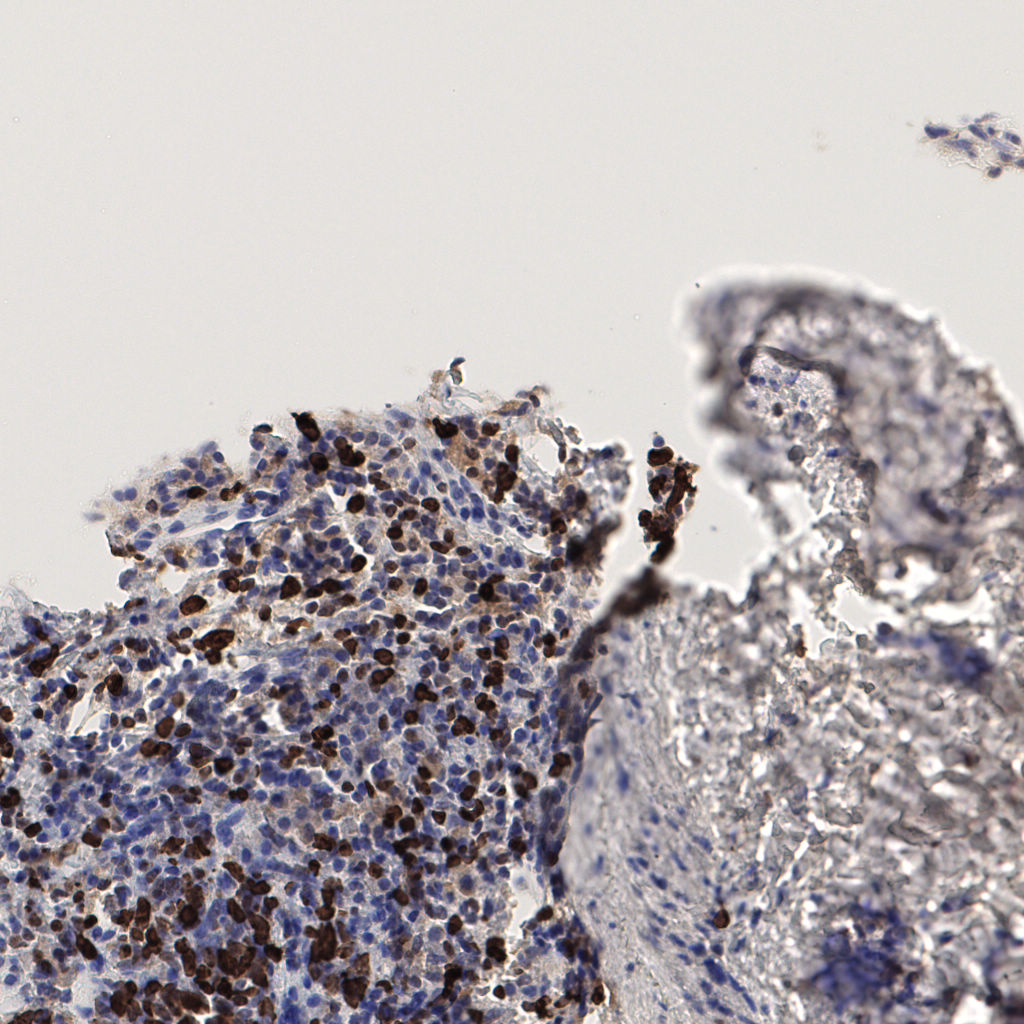

7.85%

Ki67 指数

阴 1104 阳 94

切片统计

总切片 1953

有效 288

已标记 288

有效率 15%